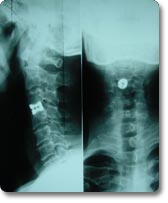

颈椎病又称颈椎综合征,是颈椎骨关节炎、增生性颈椎炎、颈神经根综合征、颈椎间盘脱出症的总称,是一种以退行性病理改变为基础的疾患。主要由于颈椎长期劳损、骨质增生,或椎间盘脱出、韧带增厚,致使颈椎脊髓、神经根或椎动脉受压,出现一系列功能障碍的临床综合征。表现为颈椎间盘退变本身及其继发性的一系列病理改变,如椎节失稳、松动;髓核突出或脱出;骨刺形成;韧带肥厚和继发的椎管狭窄等,刺激或压迫了邻近的神经根、脊髓、椎动脉及颈部交感神经等组织,并引起各种各样症状和体征的综合征。 近年来重点开展了颈椎病和腰椎间盘突出症的临床手术治疗和基础实验研究。在脊髓型颈椎病治疗方面在国内率先开展了全麻下保留颈椎终板前路颈椎间盘切除,植骨融合内固定术。又开展了经颈椎侧前路颈神经孔扩大术治疗颈神经根型颈椎病,取得了显著的临床效果。 |